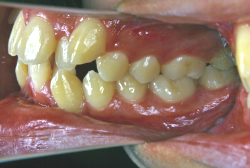

叢生(そうせい)

凸凹な歯並びのことを叢生といいます。矯正歯科に来院する患者様の主訴の中で、最も多いのが「配列の凸凹を真っ直ぐにしたい」というものです。歯の大きさと顎の大きさの調和がとれていないことが原因です。

凸凹を主体としたケースの場合、当院の平均治療期間は18ヶ月ですので、このケースは少し長めに経過しました。理由の一つは凸凹の程度がかなり重症だったと言うことですが、もう一つは、右下第2大臼歯が45度くらい前傾していたため、それを整直化させるために時間を要したと考えています。いずれにしても最終結果は大変よい状態と思います。

治療前は並びが乱れて見た目が悪いというのはもちろん問題ですが、歯科医学的に一番困るのは噛み合わせが悪いという点です。上下の犬歯(3番目の歯)は、上下的に離れた位置にあるため接触することができません。つまり歯としては存在していても、歯としては機能していないということです。